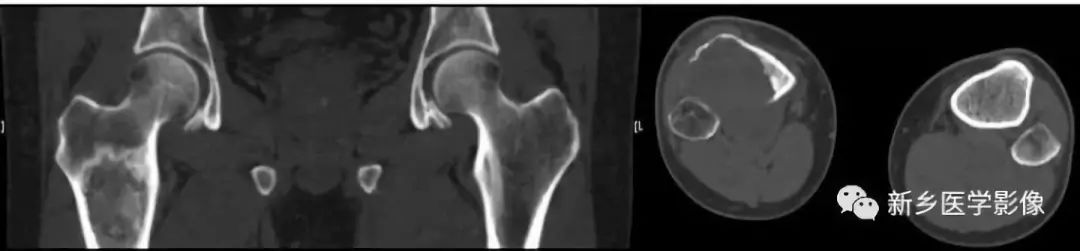

骨质破坏CT图像

a. 髋股部CT冠状面重组图像示右股骨上段骨髓腔内骨质破坏,呈膨胀性改变,周围骨质硬化;b. 小腿上段CT横断面图像示右侧胫骨大片骨质破坏、缺损,局部软组织肿块。